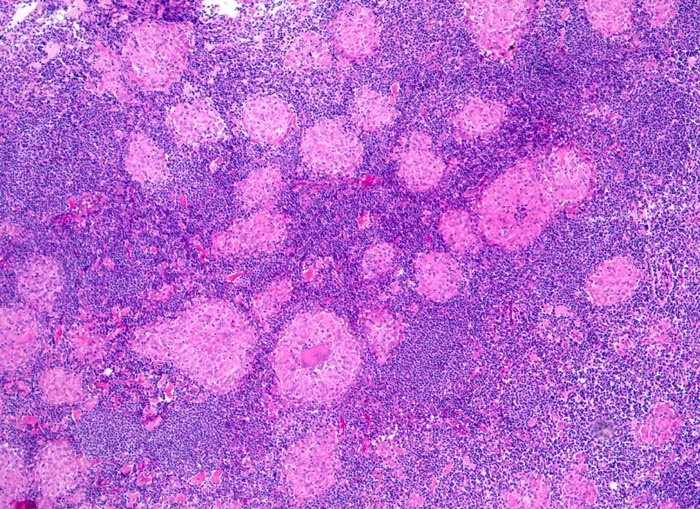

Lymphknotensarkoidose (Morbus Boeck)

Lymphknoten, inguinal

Zahlreiche nicht verkäsende Granulome durchsetzen das Lymphknotenparenchym.

Vergrösserte inguinale Lymphknoten bei bekannter Sarkoidose mit Befall der Lungen.

Histologie

50